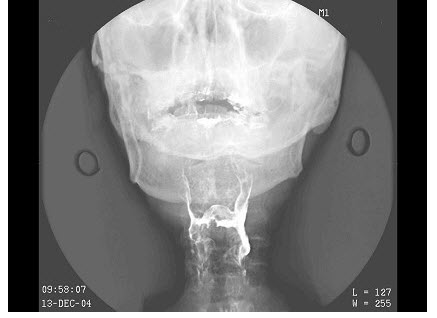

- 单项选择题女,73岁,吞咽困难2月。体检:咽充血,滤泡增生,最可能的诊断为()

- C